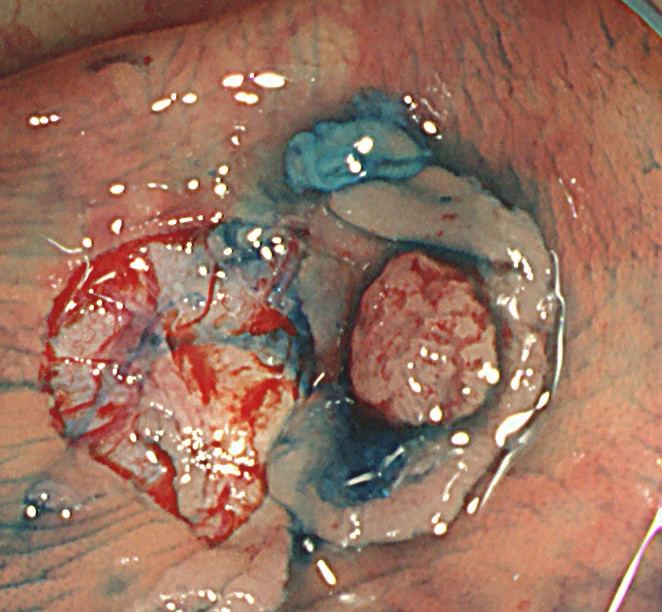

実際の写真です。

「生切り」なので、当然、内視鏡中(切除時)は出血します(患者さんが不安になります)。しかし、出血は数分で止まり、晩期出血は、まずありません。

取り残しを防ぐために、周囲に十分な余裕を持って大きく切除する必要があります(「ジャスト・サイズ」の傷では境界線上に腫瘍細胞が残ります)。そのために独特の「コツ」が必要で従来の方法よりも技術的に難しく時間がかかります。

コールド法で切除された検体は「目玉焼き」のようになります。「黄身」が病変で、「白み」が周囲の正常組織(余白、マージン)です。

腫瘍の取り残しを防ぐために「白み(余白)の大きな目玉焼き」にすることが、コールド法の最大のポイントであり、技術的に最も難しい部分です。